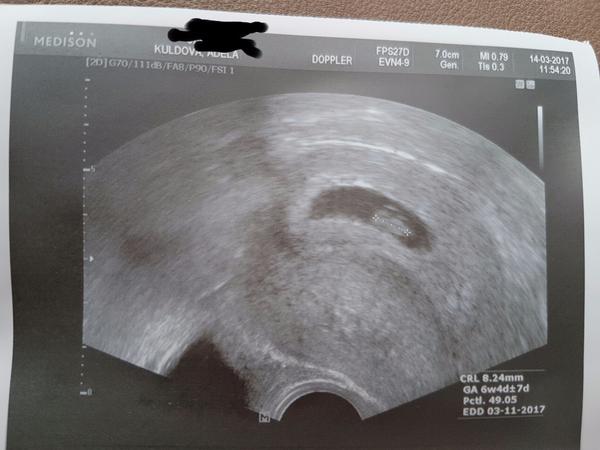

@jasmine2258 jsem ti v patach, 6+3 🙂 taky krasně bije, ta cevička 🙂))))

Holky!!! Dneska 7+1 a máme ❤👼🤰😃!!! Já mám takovou radost!!! Slyšeli jsme, jak ❤krásně bije a viděli, jak na ultrazvuku bliká!!! Přeji i vám, ať se tohoto okamžiku brzy dočkáte!!! Je to tak krásné!!! 😭😭😭❤